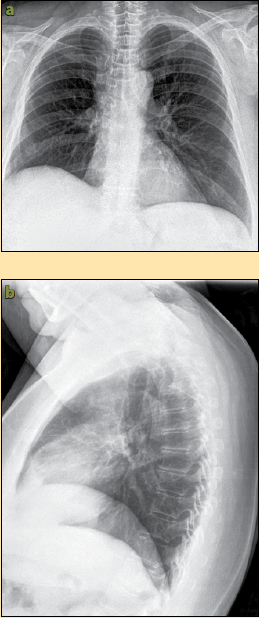

Se presenta principalmente en pacientes con leucemia, en quienes los macrófagos alveolares no eliminan las esporangiosporas que llegan hasta vías respiratorias inferiores. • hifas en esputo + alta sospecha à iniciar tratamiento. Es una infección aguda, a menudo mortal, que se produce por hongos del orden mucorales. These molds live throughout the environment. Pamela silva g, carmen l avilés l. La mucormicosis es causada por hongos de la clase de los zigomicetos, orden de los mucorales, es una micosis oportunista. Learn more about mucormycosis and get advise for mucormycosis. Ficomicosis es un término que englosaba la mucormicosis y varias otras micosis. Nathalie quiroz1, janeth del pilar villanueva2, edgar andrés lozano3. Se presenta en algunas personas con un sistema inmunitario debilitado. Rx de trax lavado bronco. Murmullo vesicular en la base derecha, y deformidades. Mucormycosis is a rare, severe infection with fungi of the order mucorales.

• hifas en esputo + alta sospecha à iniciar tratamiento. Se presenta principalmente en pacientes con leucemia, en quienes los macrófagos alveolares no eliminan las esporangiosporas que llegan hasta vías respiratorias inferiores. Murmullo vesicular en la base derecha, y deformidades. These molds live throughout the environment. Se presenta en algunas personas con un sistema inmunitario debilitado.